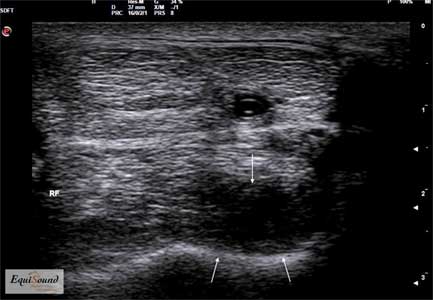

Depuis 30 à 40 ans déjà, le diagnostic des tendinopathies s’effectue à l’aide d’une échographie. Cette technique diagnostique convient très bien pour les zones où les tendons sont superficiels. Pour les structures plus profondes telles que l’insertion proximale du suspenseur du boulet et le tendon fléchisseur profond dans le pied chez le cheval, l’IRM est la technique de choix pour bien visualiser les lésions et les foyers dégénératifs. Par sa richesse de contraste, l’IRM révèle également les zones actives dans le tendon.

Clichés IRM (de gauche à droite : STIR en coupe transversale, GRE en reconstruction sagittale, PD en coupe transversale) d’un chien présentant une pathologie dégénérative chronique des fléchisseurs du carpe (fléchisseur ulnaire du carpe) où l’on peut observer un épaississement sévère du tendon qui présente un mélange d’intensités hétérogènes.

Clichés IRM (de gauche à droite : T1 en coupe transversale, T1 en reconstruction sagittale) d’un cheval présentant une desmopathie d’insertion dégénérative chronique. Hormis l’épaississement du lobe médial avec augmentation du signal T1 sur la face dorsale (fibrose), il y a chez ce cheval de nets signes de chronicité au niveau de la corticale palmaire du canon : une lésion au niveau de la face palmaire résultant de la pression chronique et une sclérose intramédullaire de la face dorsale.